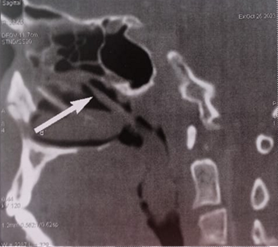

computed tomography (CT) scan of the of face revealed a mass of cystic density

filling the lumen of the nasopharynx and the upper part of the oropharynx which

was non-enhanced after contrast injection. However, all the paranasal sinuses

were clear (Figure 2). MRI of the

Figure 2. Axial and sagittal sections of a CT scan of the face: shows a mass of cystic density which is inserted into the middle turbinate and extends into the nasopharynx (a,b) and oropharynx (a,b,c).